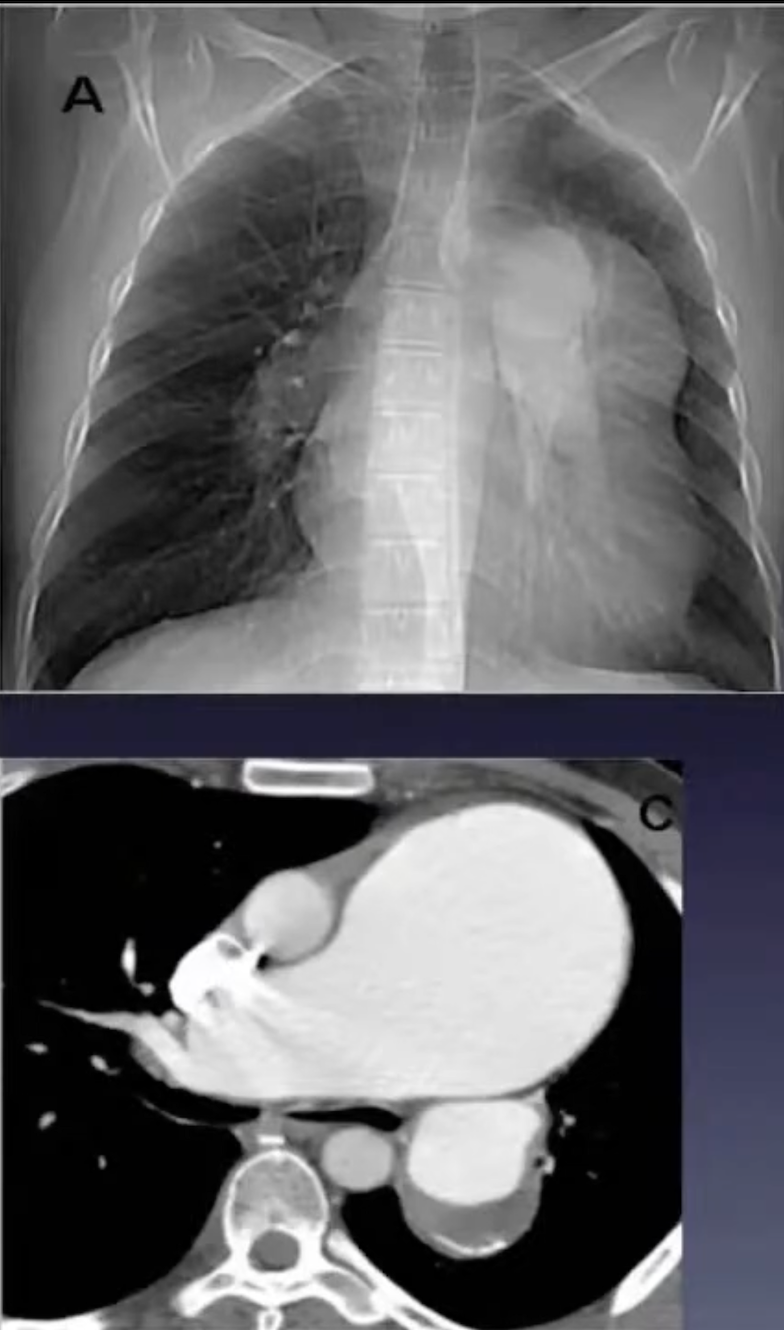

A

Hipertensão arterial pulmonar

Sinais radiológicos da HAP

• Dilatação de artéria pulmonar central

• Estreitamento abrupto ou afilamento de vasos pulmonares

• Aumento de VD e AD

• Dilatação de artérias brônquicas

• Atenuação em mosaico (perfusão pulmonar)